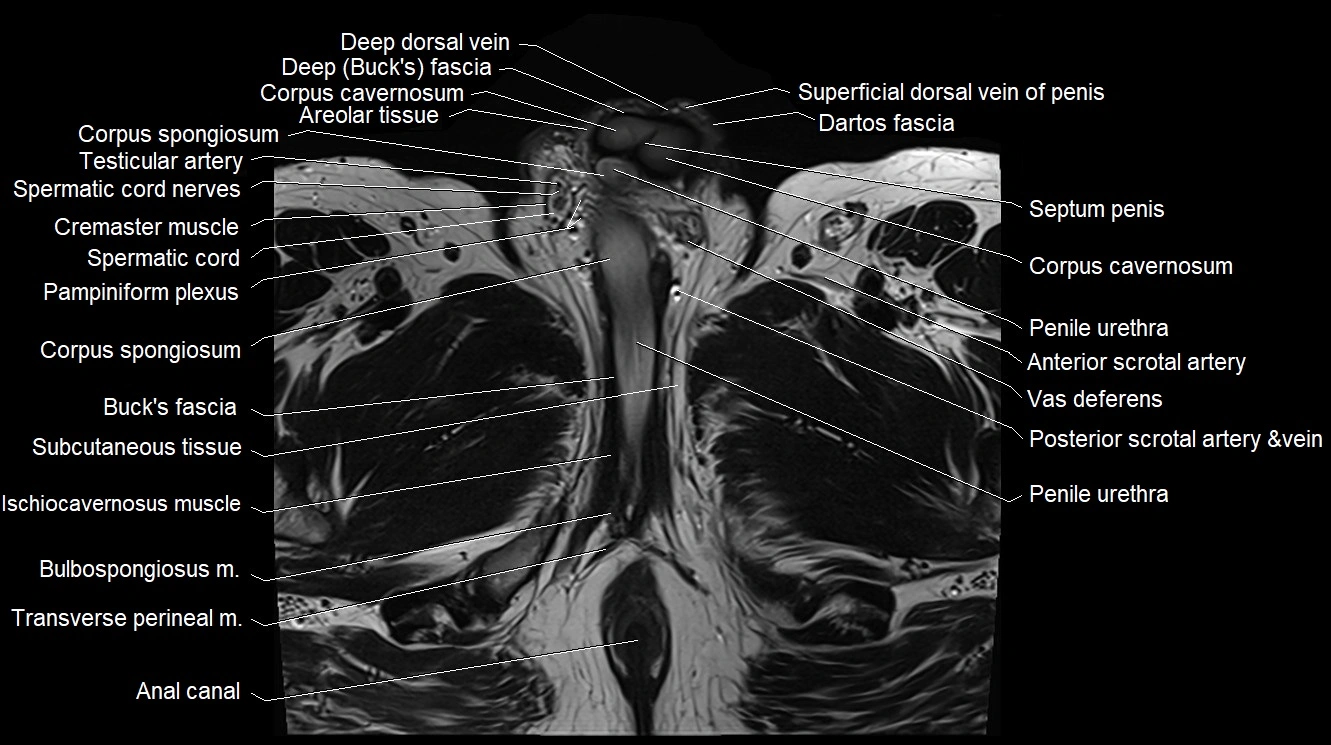

- Anal canal

- Bulbospongiosus muscle (Male)

- Corpus cavernosum

- Corpus spongiosum

- Cremaster muscle

- Dartos fascia

- Deep dorsal vein of the penis

- Deep transverse perineal muscle

- Ischiocavernosus muscle (Male)

- Pampiniform plexus

- Penile urethra

- Septum of the penis (Penile septum)

- Spermatic cord

- Spermatic cord nerves

- Subcutaneous tissue (scrotum)

- Superficial dorsal vein of penis

- Testicular artery

- Transverse perineal muscle

- Vas deferens